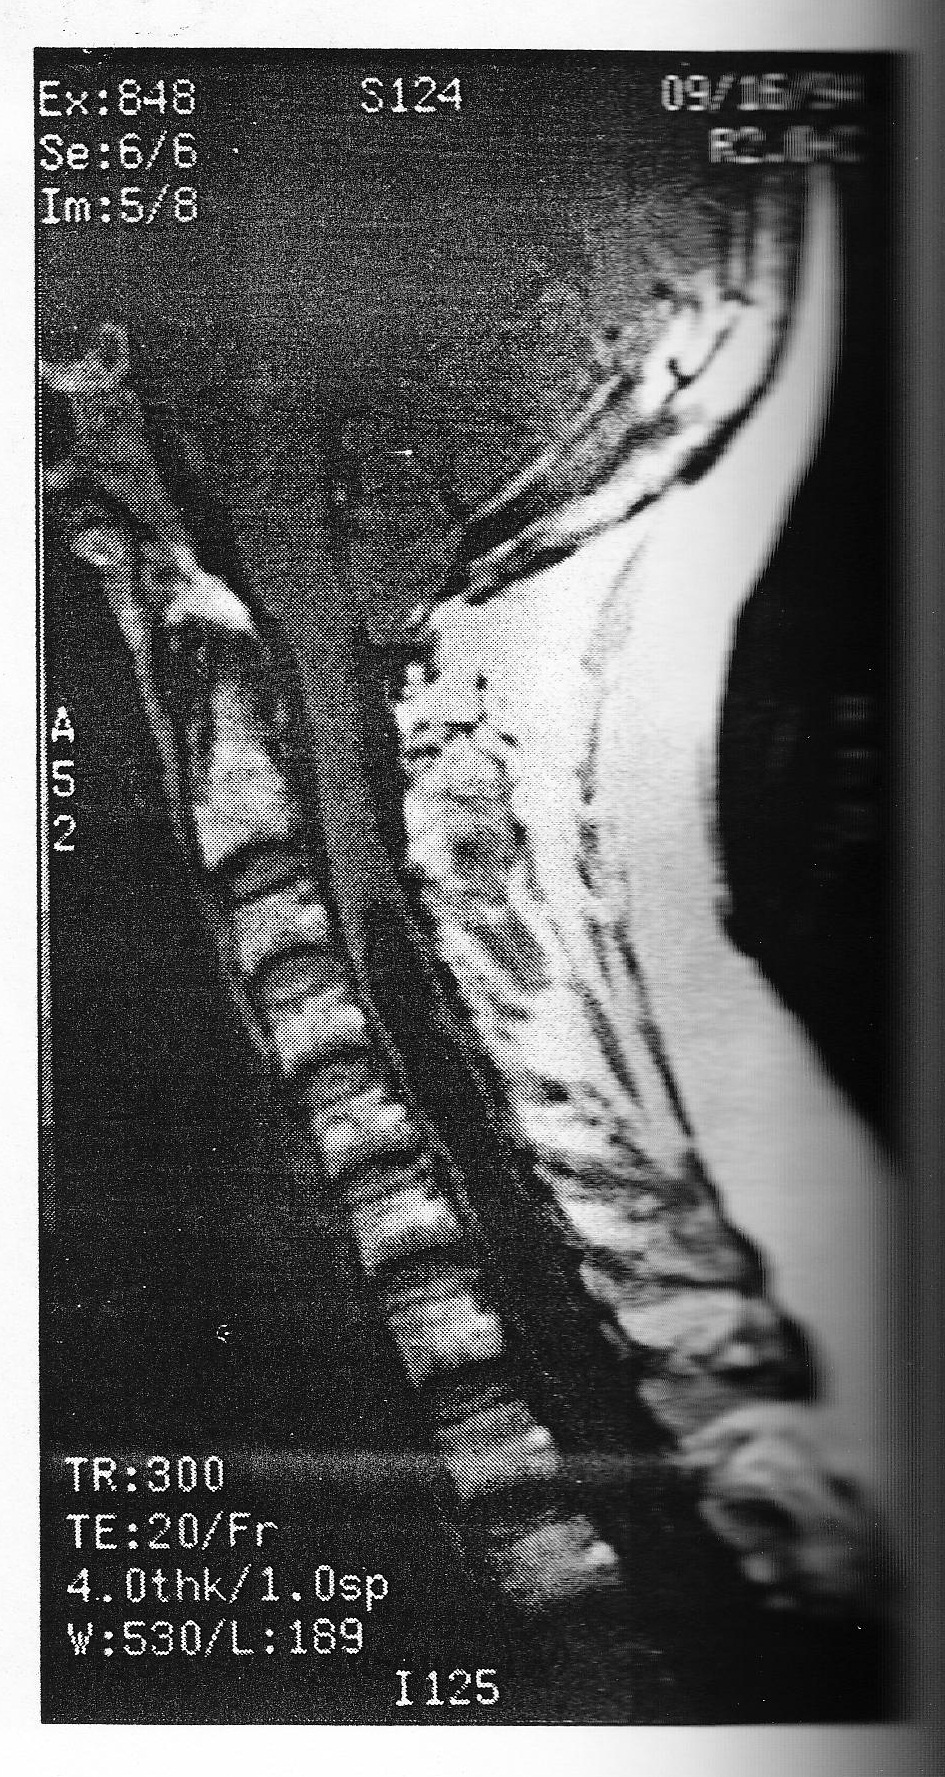

A 50-year-old female present with vague complaints of neck pain, swallowing difficulties, visual complaints, and malaise. A cervical MRI demonstrates a syringomyelic cavity extending from C4 down into the conus medullaris, with downward displacements of cerebellar tonsils (Figure 40). The patient has mild gait difficulties and nystagmus. The contrast MRI does not demonstrate evidence of neoplasm in the cervical or thoracic chord. You ADVISE the following:

A. Percutaneous needling of the hydromyelic cavity

B. Terminal ventriculostomy: opening the distal part of the fluid sac, below the conus medullaris

C. Expectant treatment with surgery reserved for worsening of sign symptoms clearly related ot the syringomyelia

D. Suboccipital craniectomy, upper cervical laminectomies, followed duraplasty to decompress the Chiary malformation

E. Further radiographic studies